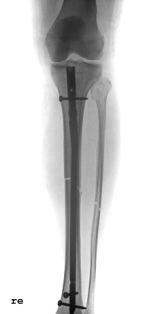

Abbildung 1: Kompletter Unterschenkelbruch bei einer 62 jährigen Patientin nach Sturz von einer Rampe.